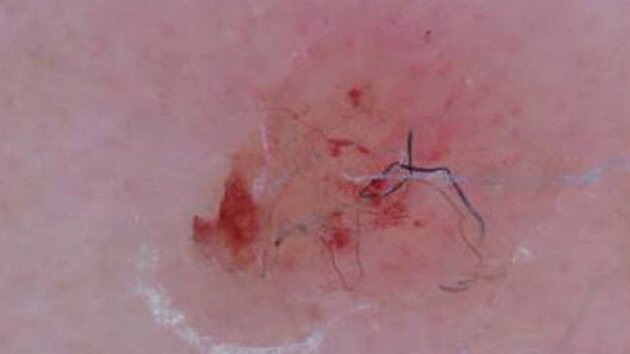

The itch nobody can scratch

A real indictment of “business as usual” where “business” is the medical industrial complex. via The itch nobody can scratch — Matter — Medium. Continue reading